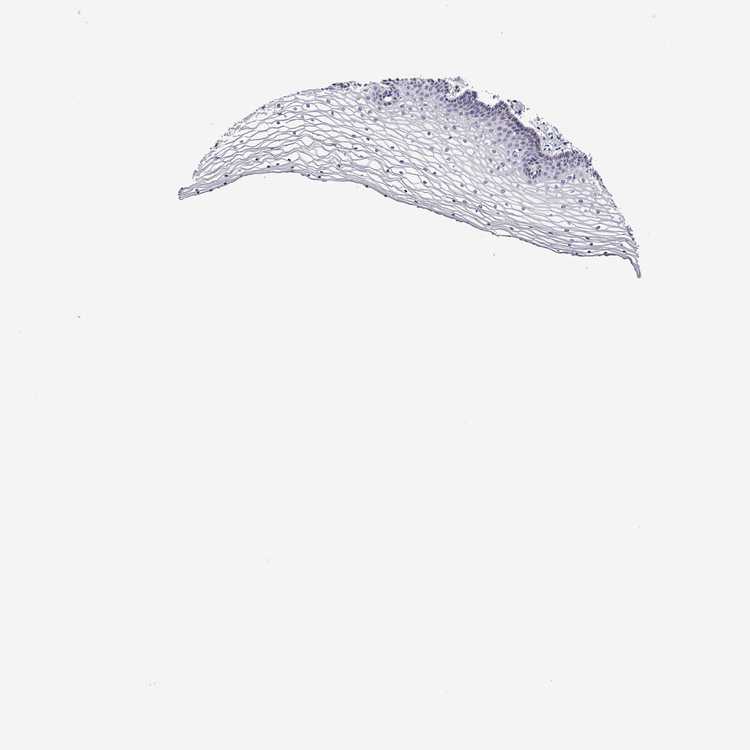

VAGINA - Antibody stainingi

Antibody staining in the annotated cell types in the current human tissue is reported as not detected, low, medium, or high, based on conventional immunohistochemistry profiling in selected tissues. This score is based on the combination of the staining intensity and fraction of stained cells.

Each image is clickable and will lead to virtual microscopy that enables deeper exploration of all samples and also displays staining intensity scores, fraction scores and subcellular localization as well as patient and tissue information for each sample.

Antibody HPA007042Antibody HPA030048Antibody CAB022682

Squamous epithelial cells Not detectedNot detectedNot detected